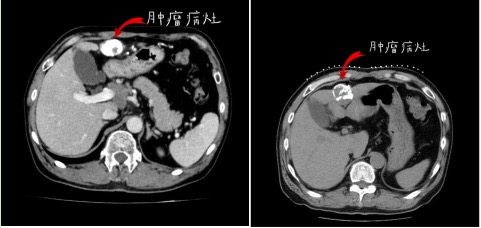

随 后,患者与沈阳市第六人民医院肿瘤介入综合科行肝组织间粒子植入,及门脉癌栓内粒子植入治疗,共植入37颗粒子,术后恢复良好出院。2020年4月8日复 查,肝增强MRI显示,病灶较前缩小,病灶内无明显强化,提示癌灶已坏死,门脉左右及主干支均通畅,肝门部及腹膜后淋巴结较前缩小。AFP 6.74 ng/ml,已降至正常。

粒子手术后4个月复查